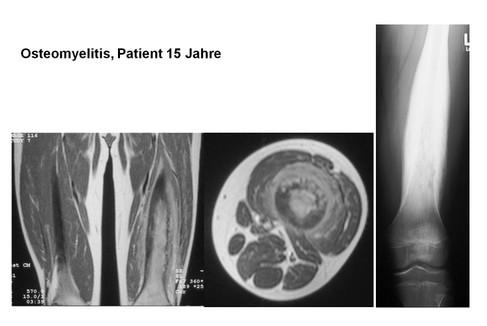

Etwa 25% der Tumoren finden sich im Femur, jeweils etwa 11% im Humerus, im Os ileum oder in der Tibia sowie an anderen Lokalisationen. Mehr als 75-90% aller Ewing-Sarkome treten vor dem 20. Lebensjahr auf. Bevorzugt werden dabei in typischer Weise die proximalen metadiaphysären Bereiche sowie der diaphysäre Bereich. Radiologisch zeigt sich ein hochpermeatives Wachstum ohne Matrixproduktion mit zum Teil erheblichen Weichteiltumoren. In einigen Fällen finden sich reaktive Knochenveränderungen mit Sklerosen oder periostale lamelläre Reaktionen mit typischem Zwiebelschalenmuster. Die Röntgenmorphologie ist dabei einer Osteomyelitis durchaus ähnlich. Das Ewing-Sarkom zeigt als extrem undifferenzierter Tumor mit hoch aggressivem Wachstum systemisch unbehandelt eine ausgesprochen schlechte Prognose. Trotz radikaler lokaler Resektion lag die bis Ende der 70er-Jahre erzielte Prognose mit einer 5-Jahresüberlebensrate von weniger als zehn Prozent und einem Überleben des ersten Jahres von weniger als 50% im frustranen Bereich. Erst durch die Einführung der Chemotherapie durch Jürgens mit der Initiierung der ersten CESS-Studie ab 1981 ließ sich die Prognose erheblich verbessern. Aktuell werden die Patienten gemäß des EUROpean Ewing tumour Working Initiative of National Groups – Ewing Tumour Studies 1999 (Euro-E.W.I.N.G 99)-Protokolls behandelt (ewing@uni-muenster.de). Prinzipiell sieht das Protokoll dabei neben der neoadjuvanten und adjuvanten Chemotherapie eine Resektion und/oder Bestrahlung des Tumors vor. Unter Zusammenfassung der bisher publizierten Erkenntnisse verschiedener Arbeitsgruppen scheint die ausschließliche Chemo- und Strahlentherapie des Ewing-Sarkoms eine um etwa zehn Prozent reduzierte Prognose gegenüber einer Chemotherapie und vollständigen Resektion des Tumors aufzuweisen. Da in vielen Fällen jedoch vor allem Läsionen mit schlecht resektablen Tumorsitz (Wirbelsäule, Becken) oder großem Tumorvolumen bestrahlt wurden, ist die Aussage umstritten. Andererseits finden sich Berichte von Sekundärmalignomen nach kombinierter Radiochemotherapie. Einiges spricht deshalb dafür, vor allem bei nicht kurativ oder nur mit erheblichem funktionellen Defizit resektablen Tumoren die Strahlentherapie ohne zusätzliche Resektion der Läsion als lokales Verfahren einzusetzen. Patienten mit prognostisch ungünstigen Risikofaktoren, wie z. B. einem schlechten Ansprechen auf eine Chemotherapie, könnten von einer zusätzlichen Bestrahlung ebenfalls profitieren. Generell zeigten die Daten der CESS 86 Studie, dass von jenen Patienten mit lokalisierter, also primär nicht metastasierter Erkrankung, nach zehn Jahren 57% noch am Leben waren. Insgesamt 52% erlitten dabei nie ein Krankheitsrezidiv. Von den 48% der Patienten mit Rezidiv der Erkrankung erlitten sieben Prozent ein Lokalrezidiv, 31 Prozent eine Metastasierung und 4% beides. An vermuteten Komplikationen der Therapie starben zwei Prozent der Patienten, ein Prozent erlitt ein Zweitmalignom. Prognostisch ungünstig zeigten sich ein Tumorvolumen von mehr als 200 ml sowie ein schlechtes Ansprechen auf die Chemotherapie. In neueren Studien zeigte sich auch die EWS-FLI1-Fusion günstiger als andere chromosomale Fusionen. Letzlich hat sich das Gesamtüberleben der Patienten mit Ewing-Sarkom in den letzten 20 Jahren wesentlich verbessert. Sie gleicht nun nahezu jener von Patienten mit Osteosarkomen. Unten stehend haben wir eine gemeinsame Arbeit angefügt, bei der wir uns gezielt mit dem nicht-metastasierten Ewing-Sarkom in einer multizentrischen Studie beschfäftigt haben.